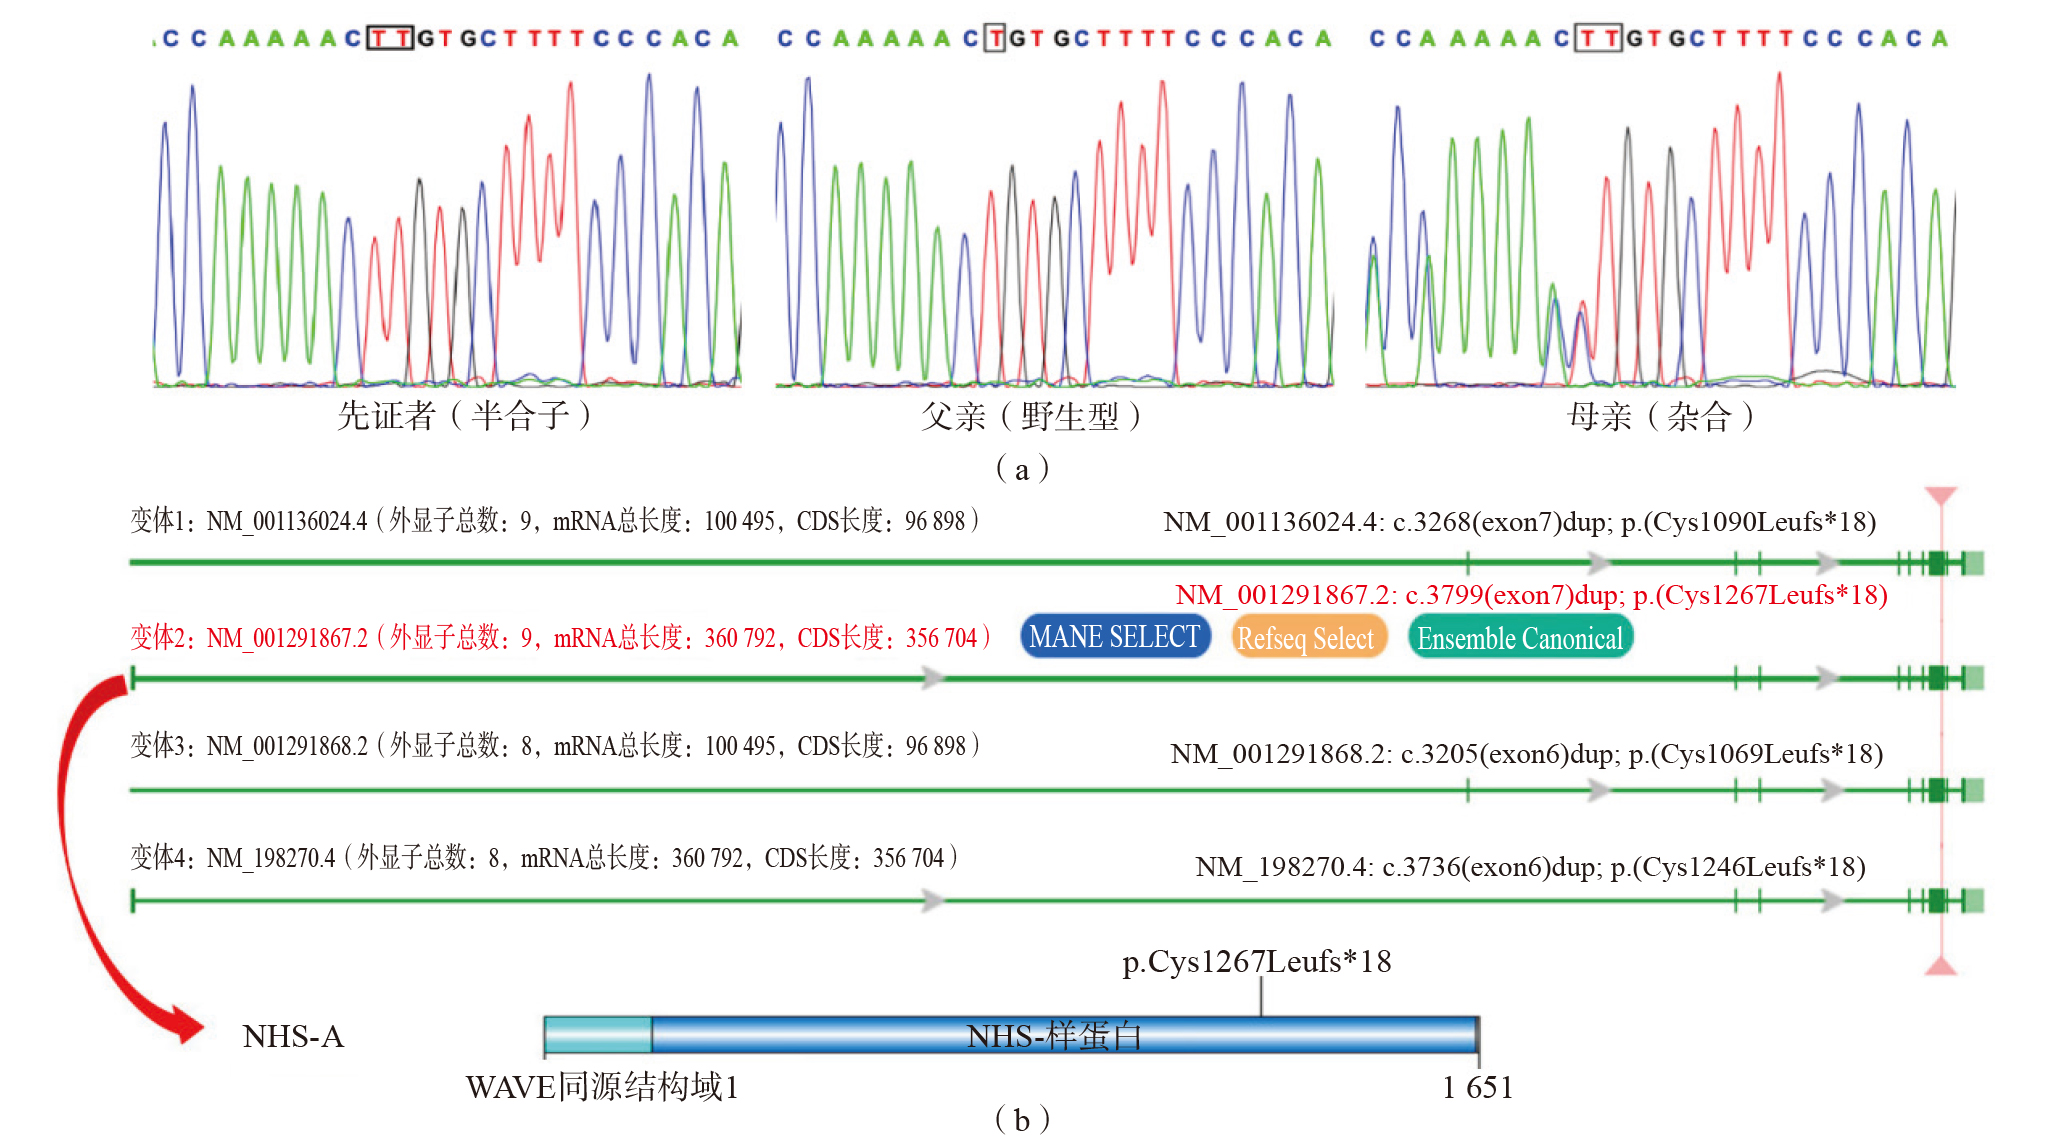

图2 胎儿及其父母Sanger测序图和基因、蛋白结构示意图 注:(a)胎儿NHS基因发生半合子变异c.3799dup(p.Cys1267Leufs*18),其母亲携带该变异,父亲为野生型;(b)NHS基因有4个转录本,以NM_001291867.2为主转录本,该胎儿半合子变异为c.3799dup(p.Cys1267Leufs*18),导致全长1 651个氨基酸的NHS-A蛋白变为1 283个氨基酸的异常截短蛋白。